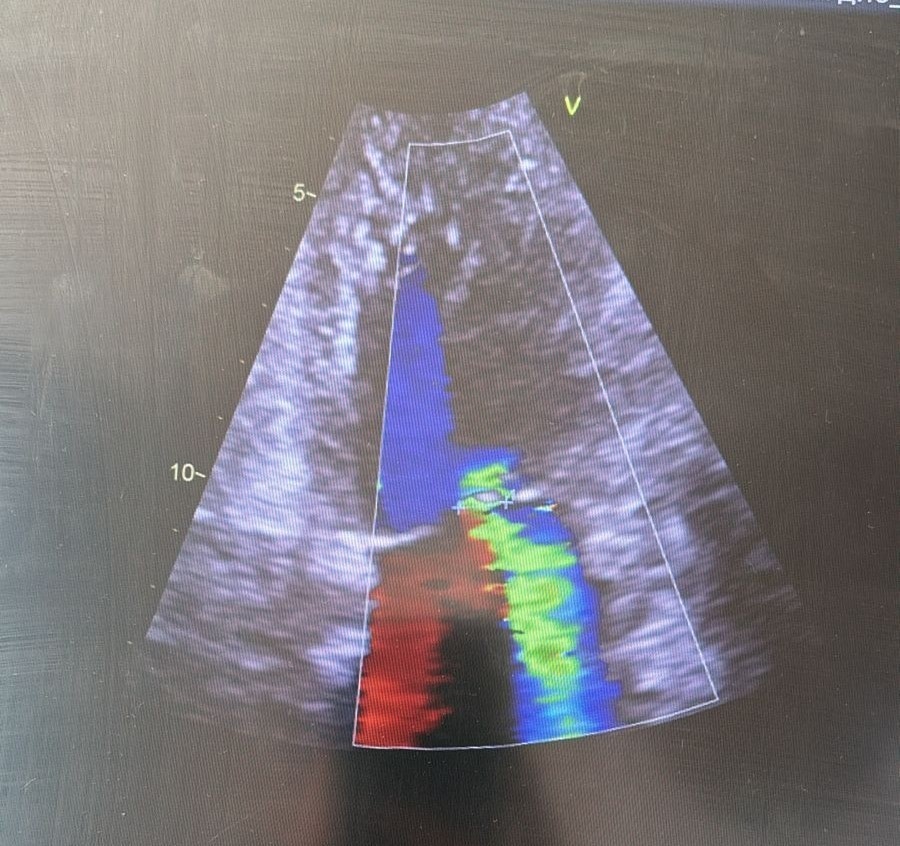

Чреспищеводная эхокардиография (ЧПЭхоКГ) — это современный метод ультразвукового исследования сердца, при котором специальный датчик вводится через пищевод. Это позволяет получить очень четкие и детальные изображения сердца и крупных сосудов, поскольку пищевод проходит непосредственно рядом с сердцем. В отличие от обычной эхокардиографии через грудную клетку, ЧПЭхоКГ обеспечивает более высокое качество изображения и позволяет выявить даже мельчайшие отклонения в работе сердца.

4. Исследование: по мере продвижения датчика врач будет получать изображения сердца с разных ракурсов. Это займет около 20–40 минут.

- Высокая точность диагностики: позволяет выявить даже небольшие изменения в структуре и работе сердца.

- Быстрота получения результатов: изображения доступны сразу, и врач может сразу же оценить состояние сердца.